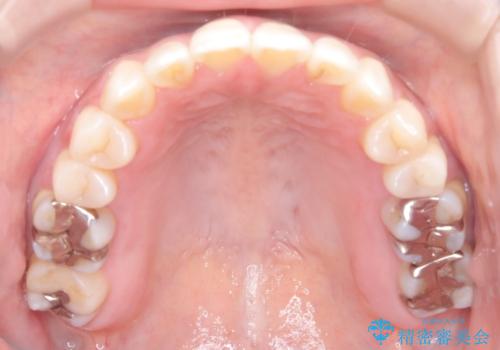

【開咬】笑った時の見た目を改善したい。

- 重度の開咬でしたがインビザラインで適切に治療計画を立て、きれいに仕上がりました。